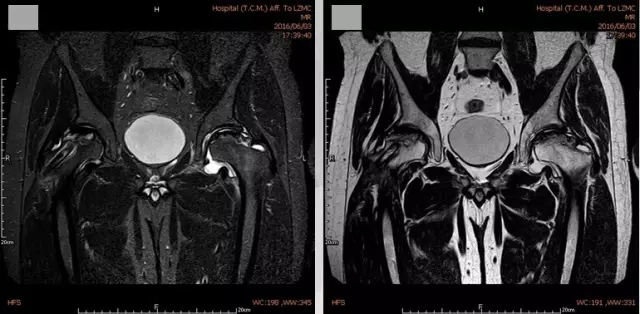

在完善相关检查后,我院关节·足踝组专家们对王某实施了吻合血管游离腓骨移植治疗股骨头缺血坏死,术后王某的情况有了明显好转。

2016年5月,王某右髋疼痛完全缓解,他再一次来到我院关节·足踝组进行了左髋手术治疗,恢复情况良好。对于专家们的精心救治,王某心中有说不出的感谢。